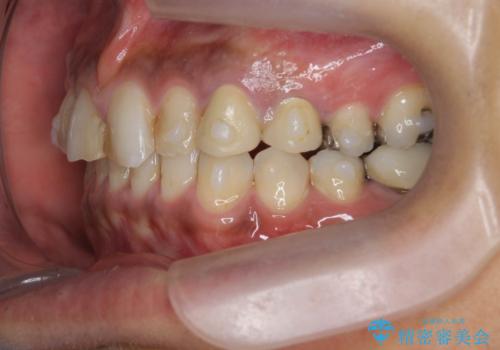

- 治療計画

- 長年虫歯の治療を受け続けたことで銀歯・コンポジットレジン修復だらけになってしまい、今後の見た目や歯を大切にするためにセラミック治療矯正治療を希望され来院されました。

マイクロスコープを用いた精密根管治療やセラミック治療、マウスピース矯正治療を一つの医院で行うことのできる当法人ならではの総合歯科治療を実践していきます。